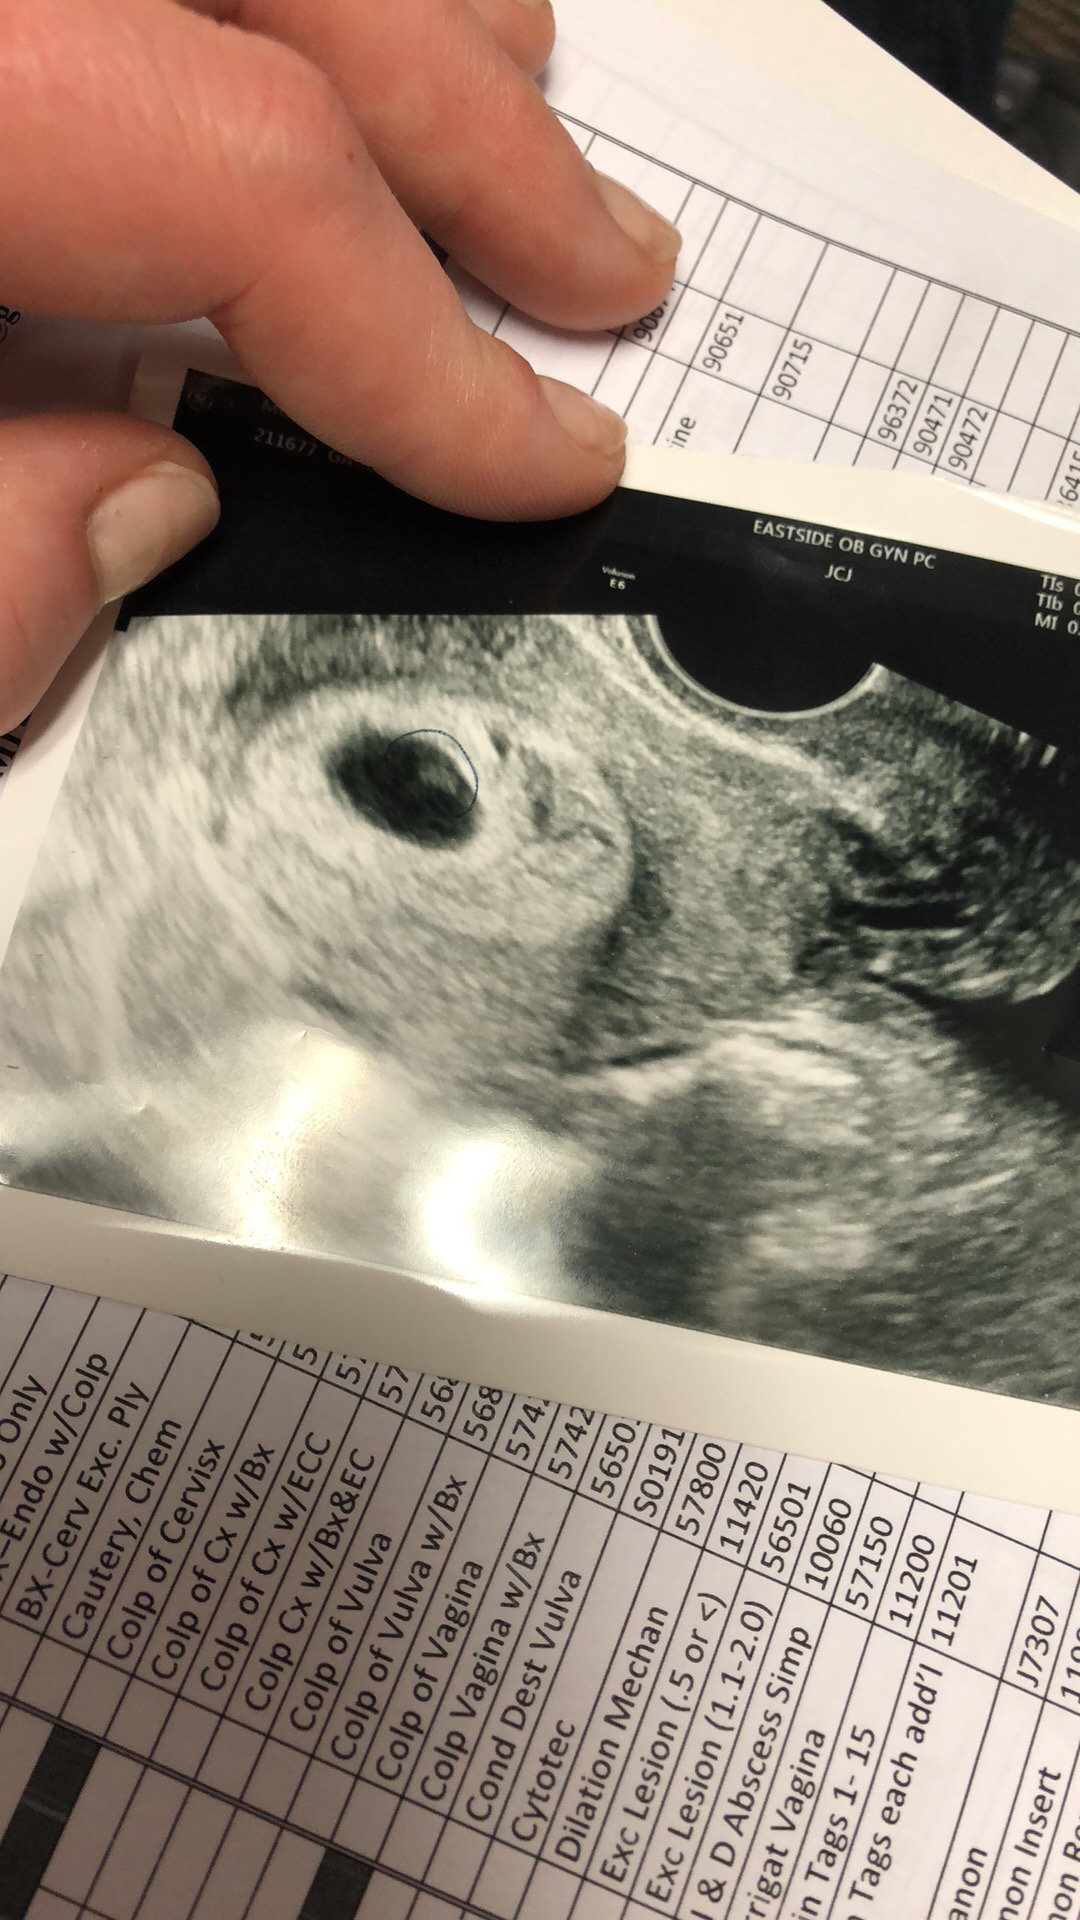

Im scheduled for my first ultrasound Friday, and I know it’s early, so I’m preparing myself for knowing there likely won’t be a heartbeat yet. I had an ultrasound at the ER last week when I went in for cramping that turned out to be gas LOL. It showed my endometrium was thick and supportive of pregnancy, and no ectopic.

Went shopping with a friend after and started having weird yellowish brown discbarge. Obviously went into panic mode and went to ER. I have to say, after that ER visit, my anxiety has calmed 110%. My cervix is high, long and tightly closed. Zero bleeding. And my beta came back at 5100. A beyond perfect rise. The doctor said that clinically, this is a perfect and healthy pregnancy. I call the office Monday to scheddule another ultrasound for during my appointment Wednesday. They said there’s a very good chance I’ll see the heartbeat then! Honestly, it’s what I’m most anxiously waiting for. I know once I see (or hear) that, I will be so reassured.

ETA: u/s photo!